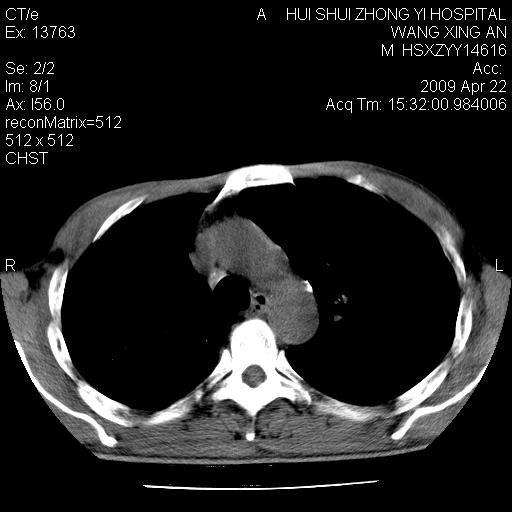

标题: CT19534:患者男、46岁咳嗽、胸痛半月。 [打印本页]

标题: CT19534:患者男、46岁咳嗽、胸痛半月。

1、右下肺中央型肺癌并右肺转移,右肺下叶不张。(肿块围绕右肺下叶支气管生长,致管腔闭塞右肺下叶不张;右肺有结节影)。

2、右侧胸腔积液。

3、右中上肺陈旧性肺结核(右肺见纤维化病灶及点状钙化)。